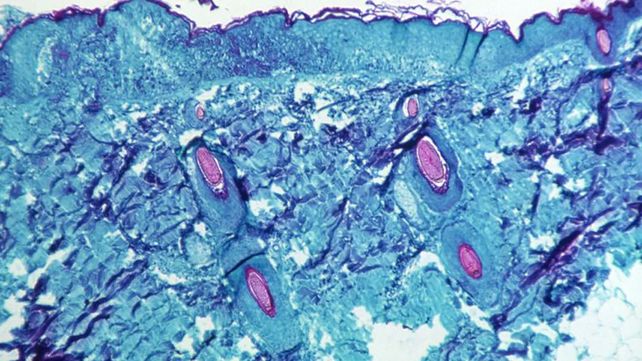

En el estudio, los investigadores utilizaron técnicas de espectrometría de masas y microscopía de superresolución para identificar y caracterizar la proteínas relevantes en el virus vaccinia, la vacuna contra la viruela, que es miembro de la misma familia de virus de la viruela símica y de la viruela humana.

Los científicos identificaron 15 nuevas proteínas dentro de los paquetes de entrega viral llamados cuerpos laterales. También localizaron cinco proteínas llamadas “redox”, que están diseñadas para interactuar con elementos del sistema inmunitario llamados especies reactivas de oxígeno (ROS). Estas son moléculas altamente reactivas que juegan un papel clave en la destrucción de patógenos identificados por el sistema inmunitario innato del cuerpo. Las proteínas “redox” dentro del virus de la viruela se liberan al comienzo de la infección específicamente para buscar y suprimir las moléculas ROS.